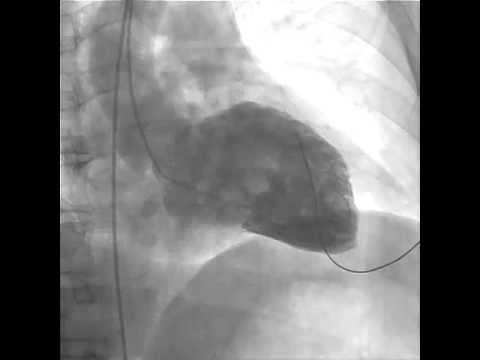

13. Ventricular Fibrillation during Left Ventriculography. :

how to treat lv dysfunction